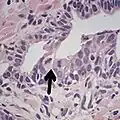

• Collagenous micronodules[4]

• Glomerulations[4]

• Glomerulations,[4] epithelial proliferations into one or more gland lumina, typically a cribriform tuft with a single attachment to the gland wall.[18]

• Perineural invasion.[4] It should be circumferential[18][notes 5]

• Angiolymphatic invasion[4]

• Extraprostatic extension [4]

Relatively common and highly specific

[4]

• Multiple nucleoli

• Eccentric nucleoli[4]